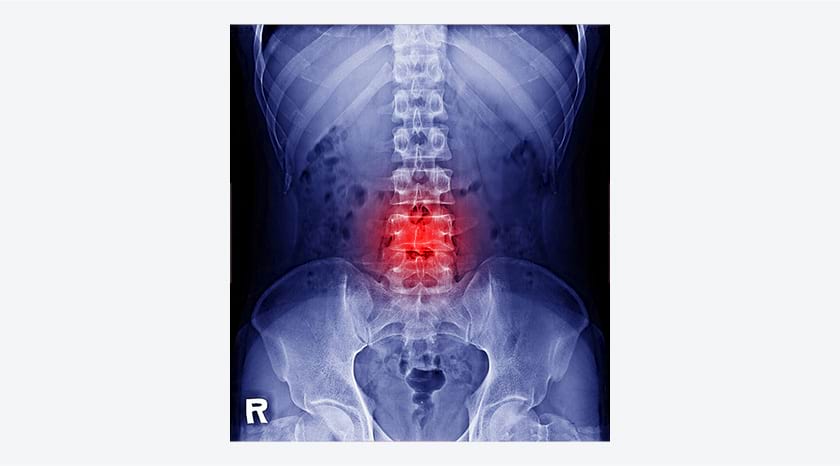

而手腕、脊椎和髖關節都是骨質疏鬆患者較易發生骨折的部位。值得留意的是,駝背和下背痛是長者常見的症狀,但這些症狀極可能是由脊椎壓縮性骨折(俗稱「冧骨」)所引致,進而導致脊椎變形。如不幸髖關節骨折,影響更大,會嚴重限制患者的行動能力。80歲以下的髖關節骨折患者中,約三成在一年後無法獨立行走,需要由家人照顧,另有二至四成需送入護老院。而髖骨骨折患者在術後1年的死亡率為17.3%,比香港同齡人口的死亡率(1.6%)約高出10倍1